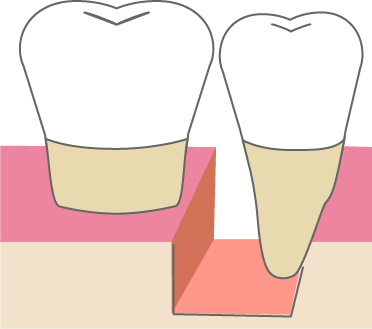

歯周組織再生療法は施術の難易度が高く、ほとんどの歯科では扱っていない内容です。

専門医資格を持つ医師が歯周組織再生治療を手がけるので、安心して治療を受けていただけます。